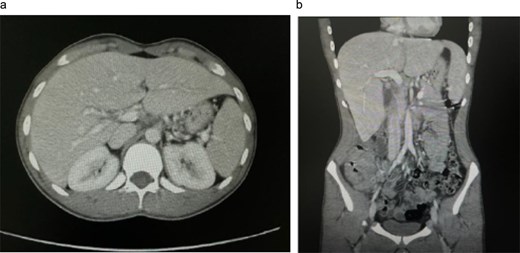

Initial contrast-enhanced computerized tomography scan of the abdomen demonstrated circumferential cecal wall thickening measuring 5.8 × 2.6 cm, a dilated appendix, and a 3.8 × 3.3 cm lesion in hepatic segment 4B, findings concerning for a right-sided colonic malignancy with hepatic metastasis. Magnetic resonance imaging (MRI) confirmed two atypical liver lesions in segments 4B and 6/7, which, in the context of right-sided colonic thickening, were considered highly suspicious for metastatic disease; biopsy of the segment 4B lesion was recommended if the colonic thickening proved non-neoplastic. Colonoscopy revealed a large fungating cecal mass (Fig. 1). Histopathological examination of biopsies demonstrated necrotizing granulomatous inflammation with fungal organisms consistent with basidiobolomycosis, and repeated biopsies confirmed the diagnosis of GIB with hepatic involvement.

Initial contrast-enhanced computed tomography (CT) abdomen. (a) Axial image demonstrating a 3.8 × 3.3 cm lesion in hepatic segment 4B, suspicious for metastasis. (b) Coronal reformatted image showing the hepatic lesion in association with right-sided colonic wall thickening, raising initial concern for primary colonic malignancy with hepatic metastasis.